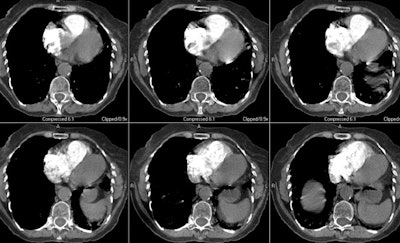

Case 8: Central PE with right heart strain.

The images below are from an elderly patient with a large embolic clot burden. There is a right main pulmonary artery embolism and the right descending pulmonary artery is completely obstructed (first image). The patient had multiple other emboli bilaterally. Note the right ventricular dilatation (in which the greatest short axis measurement of the right ventricular cavity is wider than the left ventricular cavity and the deviation of the interventricular septum toward the left ventricle (second image)- these findings are indicative of right heart strain and an increased mortality risk.